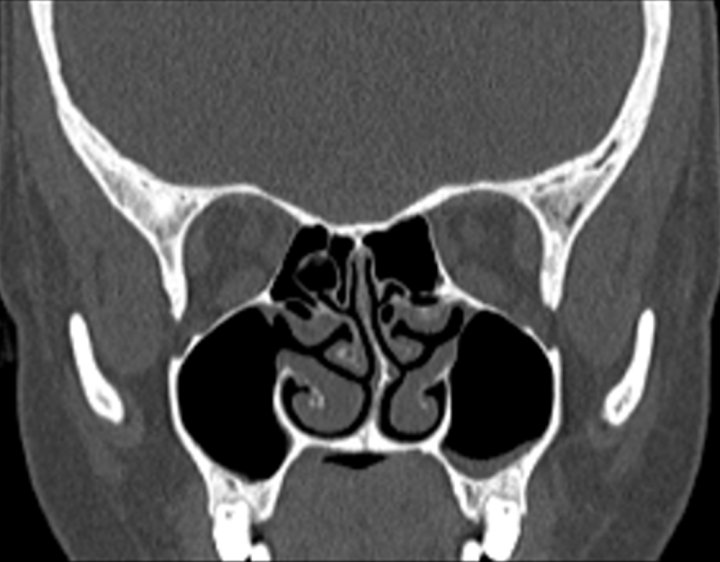

Click any image for labels.